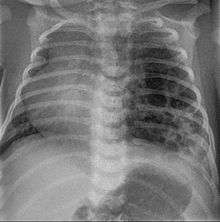

Congenital pulmonary airway malformation (CPAM), formerly known as congenital cystic adenomatoid malformation (CCAM), is a congenital disorder of the lung similar to bronchopulmonary sequestration. In CPAM, usually an entire lobe of lung is replaced by a non-working cystic piece of abnormal lung tissue. This abnormal tissue will never function as normal lung tissue. The underlying cause for CPAM is unknown. It occurs in approximately 1 in every 30,000 pregnancies.[1]

In most cases the outcome of a fetus with CPAM is very good. In rare cases, the cystic mass grows so large as to limit the growth of the surrounding lung and cause pressure against the heart. In these situations, the CPAM can be life-threatening for the fetus. CPAM can be separated into five types, based on clinical and pathologic features.[2] CPAM type 1 is the most common, with large cysts and a good prognosis. CPAM type 2 (with medium-sized cysts) often has a poor prognosis, owing to its frequent association with other significant anomalies. Other types are rare.[3]

CPAMs are often identified during routine prenatal ultrasonography. Identifying characteristics on the sonogram include: an echogenic (bright) mass appearing in the chest of the fetus, displacement of the heart from its normal position, a flat or everted (pushed downward) diaphragm, or the absence of visible lung tissue.

CPAMs are classified into three different types based largely on their gross appearance. Type I has a large (>2 cm) multiloculated cysts. Type II has smaller uniform cysts. Type III is not grossly cystic, referred to as the "adenomatoid" type. Microscopically, the lesions are not true cysts, but communicate with the surrounding parenchyma. Some lesions have an abnormal connection to a blood vessel from an aorta and are referred to as "hybrid lesions."

The earliest point at which a CPAM can be detected is by prenatal ultrasound. The classic description is of an echogenic lung mass that gradually disappears over subsequent ultrasounds. The disappearance is due to the malformation becoming filled with fluid over the course of the gestation, allowing the ultrasound waves to penetrate it more easily and rendering it invisible on sonographic imaging. When a CPAM is rapidly growing, either solid or with a dominant cyst, they have a higher incidence of developing venous outflow obstruction, cardiac failure and ultimately hydrops fetalis. If hydrops is not present, the fetus has a 95% chance of survival. When hydrops is present, risk of fetal demise is much greater without in utero surgery to correct the pathophysiology. The greatest period of growth is during the end of the second trimester, between 20–26 weeks.